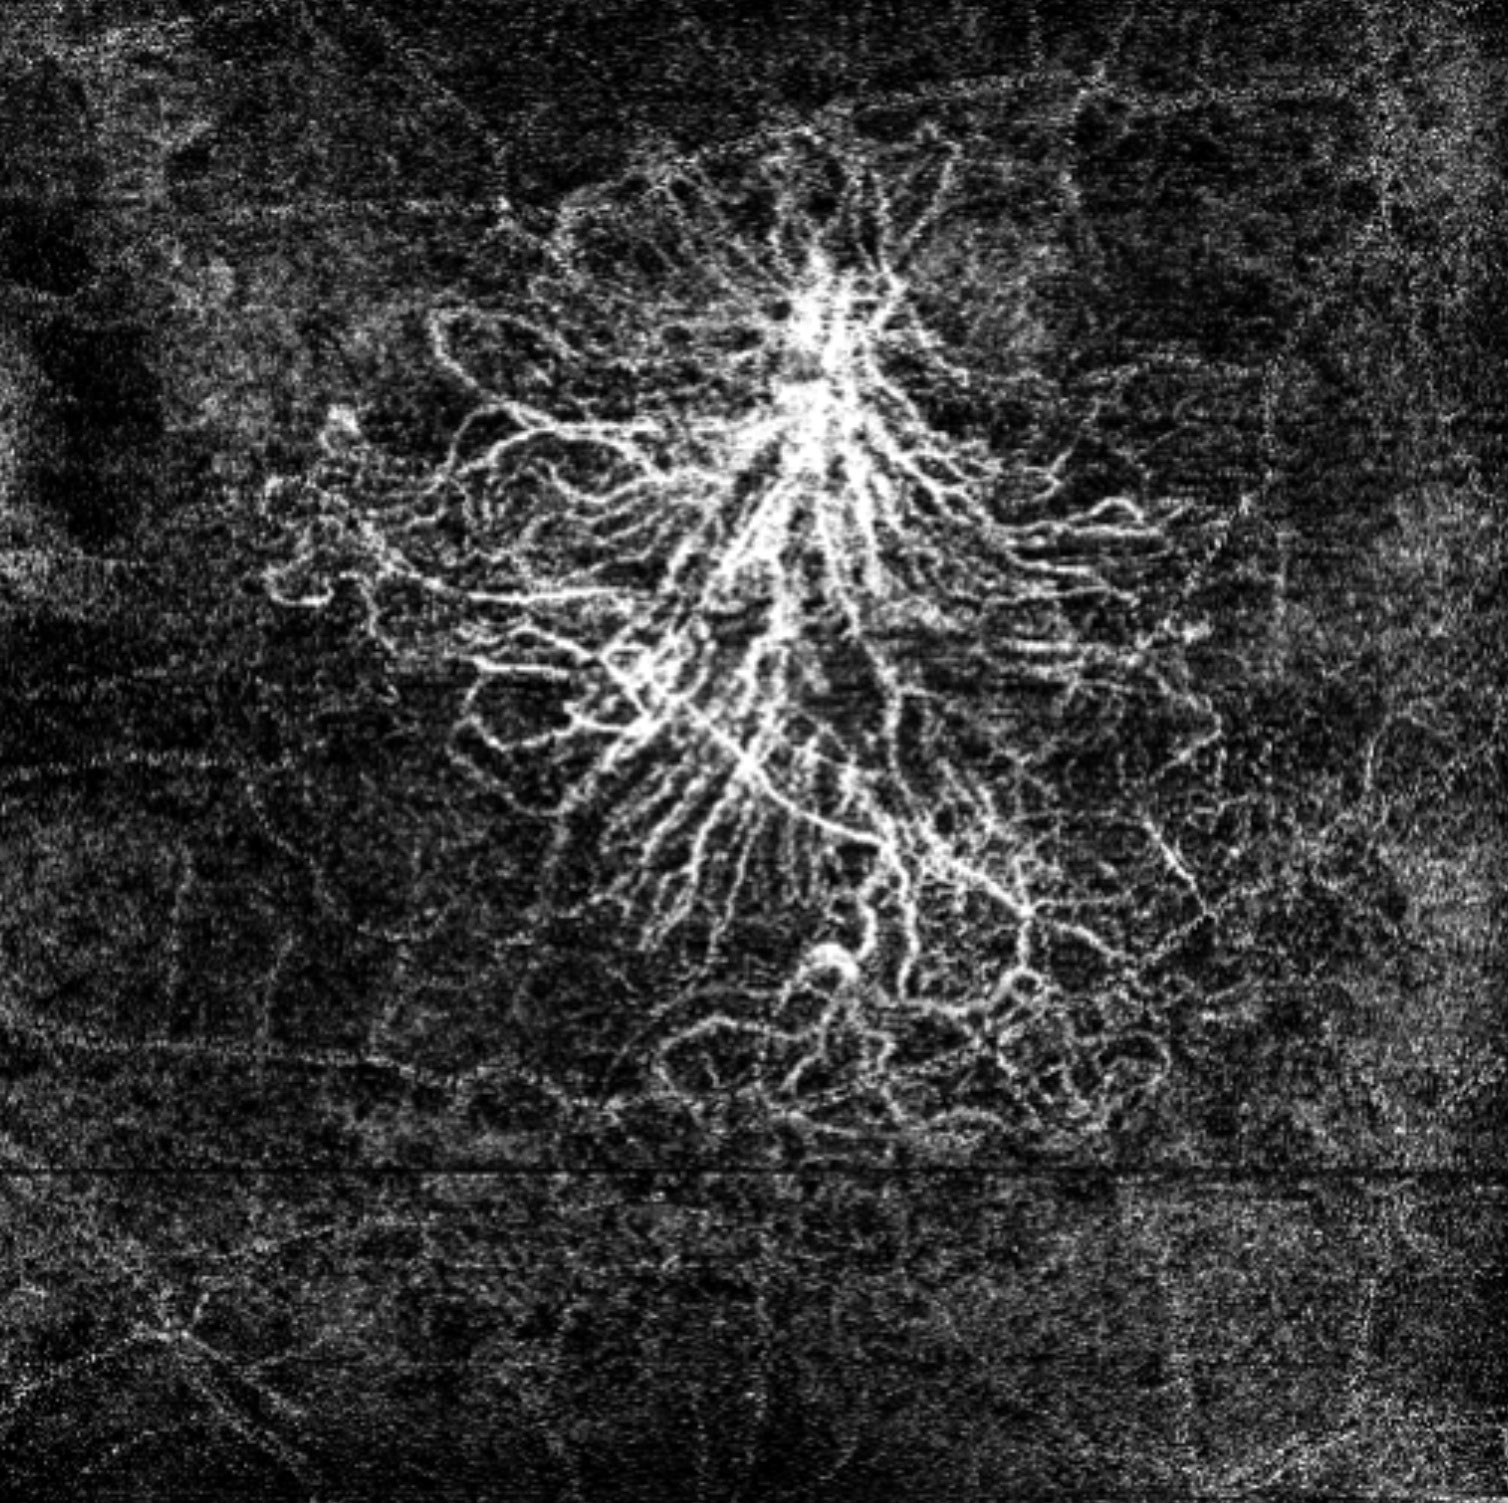

Offering the ideal speed-quality ratio for OCTA, 125 kHz allows you to increase your throughput without any clinically relevant loss in image quality in comparison to the current 85 kHz scan speed. The fast acquisition of images allows for visualization of flow, even in miniscule vessels, while minimizing artefacts, resulting in sharp and detailed images of the capillary network. Additionally, you can decrease chair time when you speed up acquisition with the Glaucoma Module Premium Edition in your glaucoma workflow, if applicable.

125 kHz – A fast scan speed for improved workflow and high OCTA image quality.